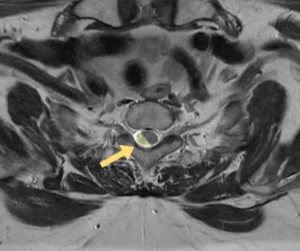

Проведённая МРТ грудного отдела позвоночника выявила две интрадуральные экстрамедуллярные опухоли, вызывающие критическую компрессию спинного мозга. Эти образования были диагностированы за 2–3 года до обращения. Однако, пациентка отказывалась от операции из-за страха, возраста и избыточного веса.

Учитывая возраст пациентки, общую соматическую нагрузку, прогрессирующую неврологическую симптоматику и необходимость срочно устранить компрессию спинного мозга, было принято решение о симультанном (одновременном) удалении обеих опухолей. Это решение позволило сократить время нахождения пациентки под наркозом и минимизировать риски. В таких случаях, когда дорога каждая минута, на помощь приходит спинальная хирургия с использованием современных технологий.

Операция была выполнена двумя командами нейрохирургов онкологов, работающих синхронно через разные хирургические доступы. Мы применили микрохирургическую технику, интраоперационный нейромониторинг и современное анестезиологическое обеспечение. Эти технологии позволили провести вмешательство максимально безопасно, сократить его длительность и уменьшить общую нагрузку на организм пациентки.